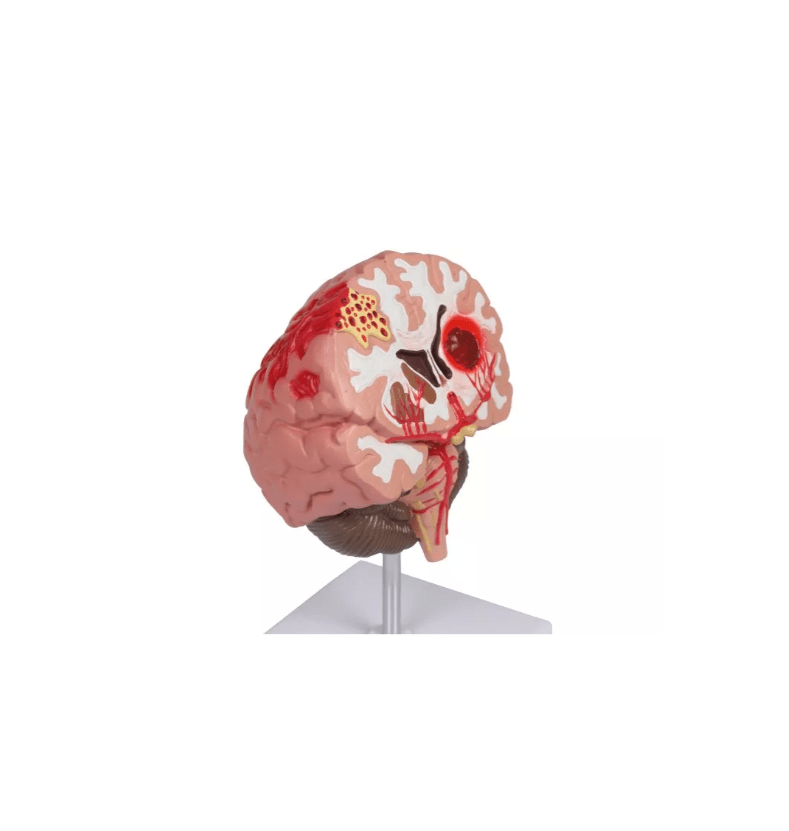

Erler-Zimmer

Pathologien des Gehirns, lebensgröße

Artikelnummer: SKU: EZC711

PZN: PZN:

Packaging unit: VE:

Auf Lager: In 1–3 Werktagen geliefert

★★★★★ 0 Bewertungen135,00 €135,00 €135,00 € -